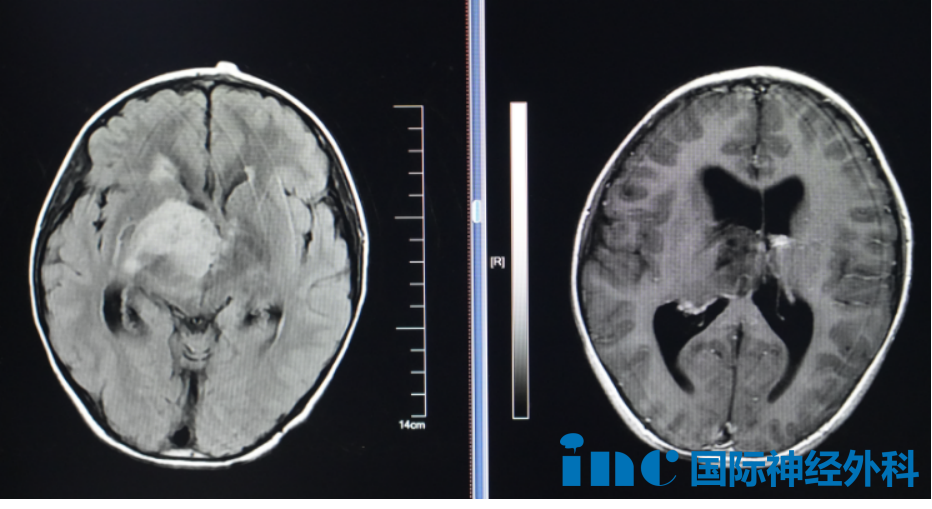

正式抵达苏州大学附属儿童医院的巴教授立即投入工作,今日需会诊8岁脑瘤患儿小航,终于迎来巴教授示范手术时机。尺寸约4.0cm×4.7cm×4.8cm的病灶占据患儿右侧丘脑区域,并已引发脑积水并发症。

因手术技术条件限制,相当比例丘脑肿瘤患者选择活检联合放化疗的治疗模式。至今仍有多数医学观点认为丘脑区域属于手术禁区,不宜实施手术。主要因其解剖结构复杂且生理功能重要,致使手术风险远大于潜在获益。然而国际神经外科专家Helmut Bertalanffy(巴特朗菲)教授早在1991年已成功发表丘脑相关手术案例。巴特朗菲教授特别擅长丘脑手术,拥有丰富高难度疑难位置脑瘤手术经验。以下为巴教授部分国内示范手术案例: